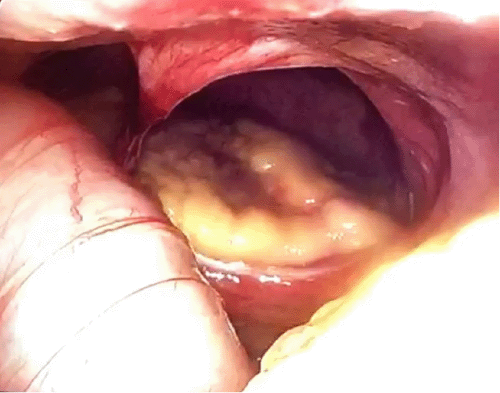

She was taken to the operating room for repair of the hernia. The operation was initially attempted laparoscopically but was converted to an open procedure due to difficulty with exposure. The hernia defect was found to be just left of the central tendon (Figure 2). The defect occupied approximately one-half of the left diaphragm. A portion of the colon was incarcerated through the defect within the pericardium. Upon reduction of the colon, the heart could be visualized through the defect. It was repaired primarily with a polyester suture (Ethibond, Ethicon, Somerville, NJ). A 10 × 15 cm polypropylene mesh (Ventralight, a subsidiary of C.R. Bard, Inc, Warwick, RI) was also placed and secured with polyester suture (Ethibond, Ethicon, Somerville, NJ).

Figure 2. Intraoperative View of Hernia. Published with Permission

Diaphragmatic defect was visualized intraoperatively; heart could be visualized through defect on left side of diaphragm